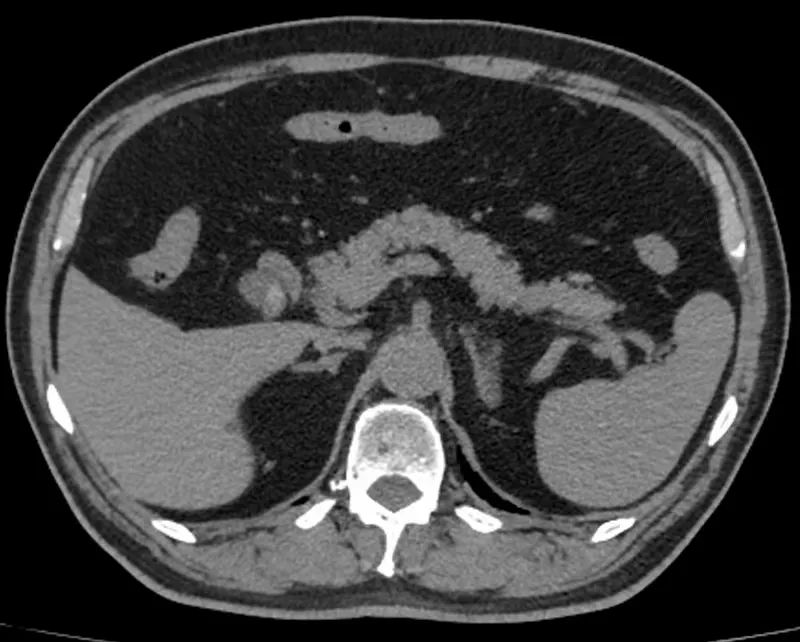

考虑到王老先生高龄加上心血管系统基础疾病,术前普外医师团队和麻醉团队进行了详尽准备。在术前影像学检查的精准导航下,段琨副主任医师带领手术团队,凭借精湛的腹腔镜技术和丰富的临床经验,精细解剖胆囊三角区,完整切除病变胆囊,仔细止血胆囊床,探查确认胆总管无损伤,手术过程顺利,术后患者生命体征平稳。因腹腔镜手术创伤小、术中出血少、术后疼痛轻、恢复快、疤痕小等优点,王老先生第二天即可下床活动,第三天腹腔引流管拔除,经过一周的精心治疗及护理顺利出院。王老先生表示,“在手术室,麻醉科李虎主任认真负责风趣幽默,缓解我的紧张情绪,让我在手术台上放松下来。手术体验也比预想好得多,术后几乎无明显不适。”